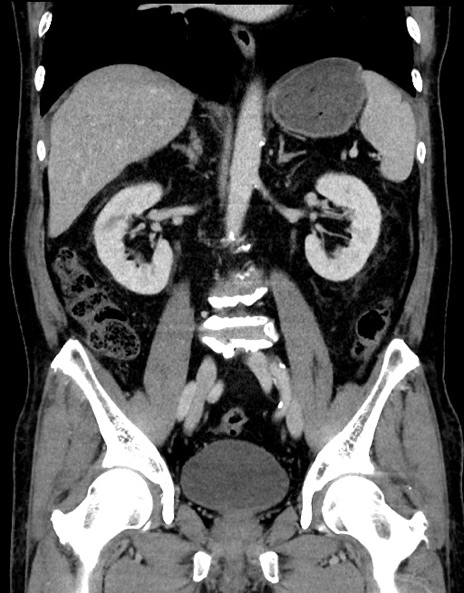

症例15(冠状断像)

【症例】70歳代男性

【主訴】腹痛

【現病歴】今朝から腹痛あり。全体的に痛い。特に左上の方。排ガスが今日はない。冷や汗が出る。

【既往歴】直腸癌術後

【身体所見】左側腹部〜上腹部に圧痛あり。腹膜刺激症状明らかなではない。軽度反跳痛。左下腹部に術後瘢痕あり。

【データ】WBC 7700、CRP 0.02